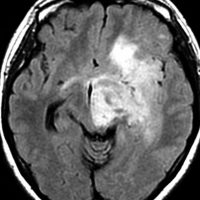

2000年頃の例です。てんかんで発症した20代の女性です。左前頭葉のグリオーマで,手術でほとんどで摘出 subtotal removalして,深部白質に残った病変を経過観察しました。MRIは術後のものです。Ip, 19qはFISHで欠失なし。MIB1は1-2%と低く,MGMTメチレーションなし,diffuse astrocytoma WHO grade 2と組織診断されました。大学病院でしたが当時はIDH遺伝子診断はしておらず,びまん性星細腫グレード2でした。これもまた当時の標準的な考えで,進行があるまでは経過観察としました。

2年後に急激な進行 rapid progressionしました。ガドリニウム増強所見も出現しました。IMRTで59.4Gy/27分割の放射線治療とテモゾロマイド化学療法をしましたが,腫瘍は抑制できませんでした。

放射線治療後も進行して,白質に沿った浸潤伸展をしました。脳幹部橋の右側まで浸潤 invasionしています。この伸展は星細胞系腫瘍の特徴でもあります。

2016年分類では,diffuse astrocytoma WHO grade 2です。しかしこれはおそらく,2021年分類では IDH wild-type astrocytoma grade 4とされます。